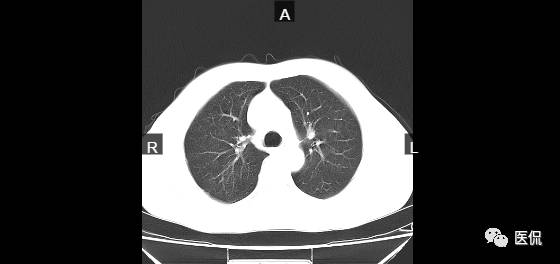

病例一

患者信息:男,60岁

检查部位:胸部

检查方法:胸部CT平扫

患者主诉:左侧胸部疼痛二十天左右,暂无其他不适症状。

影像所见:

CT平扫胸廓对称,肺窗显示两肺纹理清晰,走向分布无异常,右肺中叶及下叶见数个小结节,密度均匀,边界清楚,大小约3x3mm;纵隔窗显示两肺门无增大,气管支气管通畅,纵隔未见肿大淋巴结,胸膜、肋骨及胸壁软组织未见异常。

诊断意见:

右肺中叶及下叶数个结节:炎性?转移瘤?建议复查。